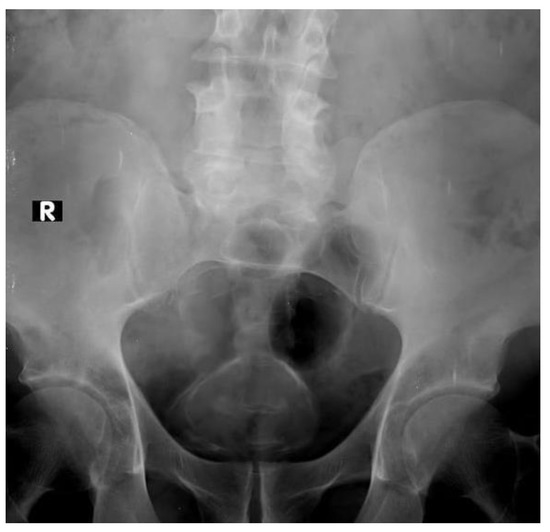

Diagnosis and staging are often achieved using multiple modalities including cytology cystoscopy with transurethral resection computerized. The prostate is enlarged. Urinary stasis and chronic inflammation increases the risk of bladder carcinoma due to mucosal dysplasia followed by tumor degeneration.

Urothelial carcinoma arising in a bladder diverticulum UCBD is uncommon and data on treatment and outcome are sparse. Imaging plays an important role in diagnosing and staging the disease. The surgical technique for treating bladder cancer in a patient with bladder diverticulum depends on many factors including the stage grade and number of tumors.

The 8th edition of the American Joint Committee on Cancer has updated the staging schema for bladder cancers with concomitant prostatic stromal invasion and cancers within bladder diverticula. 1 Bladder diverticula are either congenital or acquired and are caused by a defect of the bladder wall and increased intravesical pressure. Based on cystoscopic evaluation bimanual examination and computerized tomography.